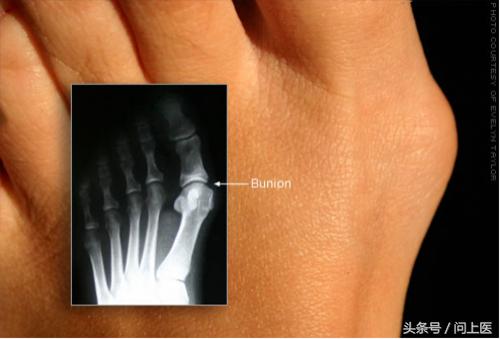

2 / 8 拇囊炎

患拇囊炎时,连接大拇指的骨头肿大而向外突出,这会导致脚骨头不正,引发关节炎而疼痛,也可能导致鸡眼。止痛药、定制的鞋垫或手术治疗可能有帮助。应穿宽松的鞋子并避免穿高跟鞋。